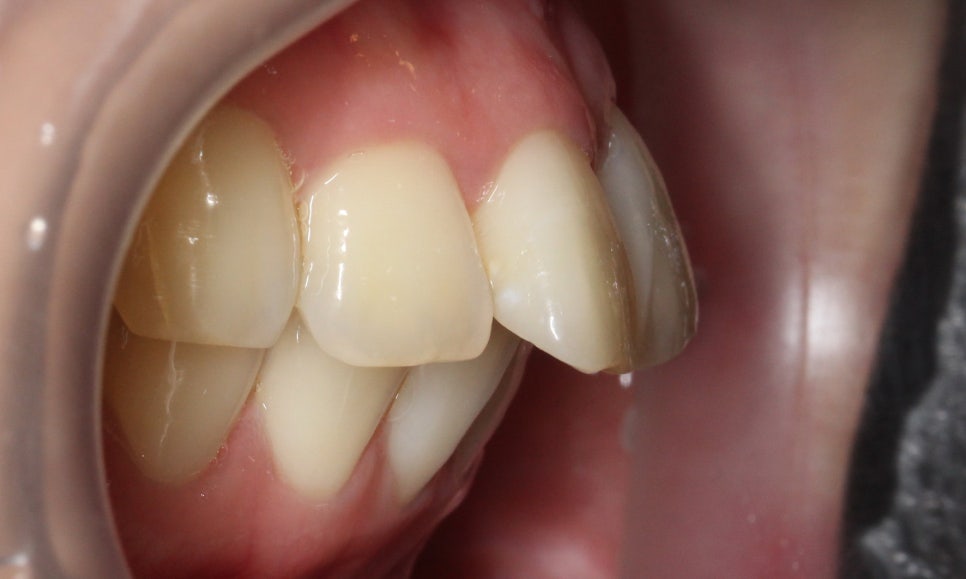

좌우 교합 평면의 모습을 보면

협측 사진에서 중절치의 돌출감이

심한 모습을 볼 수 있는데요,

구치부의 교합 상태를 보니

윗니가 과도하게 앞으로

튀어나와 있는 2급 부정교합이

의심되는 모습입니다.

이러한 경우 전치부 교정만으로는

상하악 교합을 바르게 교정하기 어려운데요,

따라서 전체교정으로 치열을 가지런하게

바꾸고 상하악 교합도 정상적으로 맞출 수 있습니다.